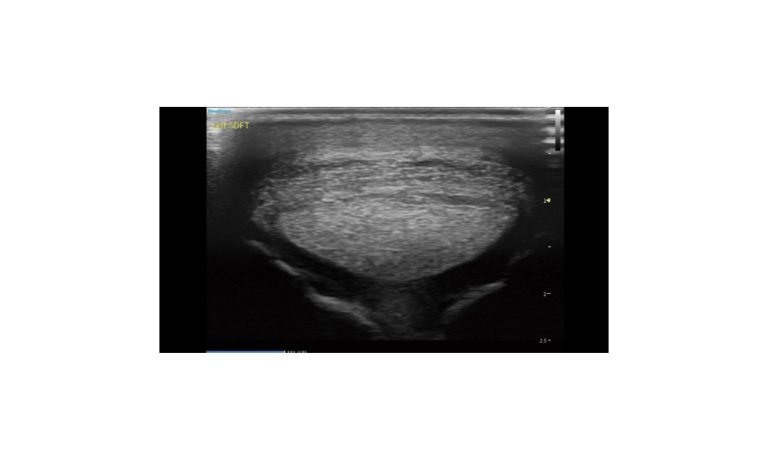

Esaote MyLab Sigma; So Fast, So Easy

Esaote’s new MyLab™SigmaVET is the smart, portable solution that allows use of an ultrasound whenever a quick and complete diagnosis is required.

- Dedicated VET software and probes

- Windows® 10

- Quick start-up

- Highly responsive capacitive touchscreen

- Pivoting 15.6” monitor2 probes connectors

- Easy to carry